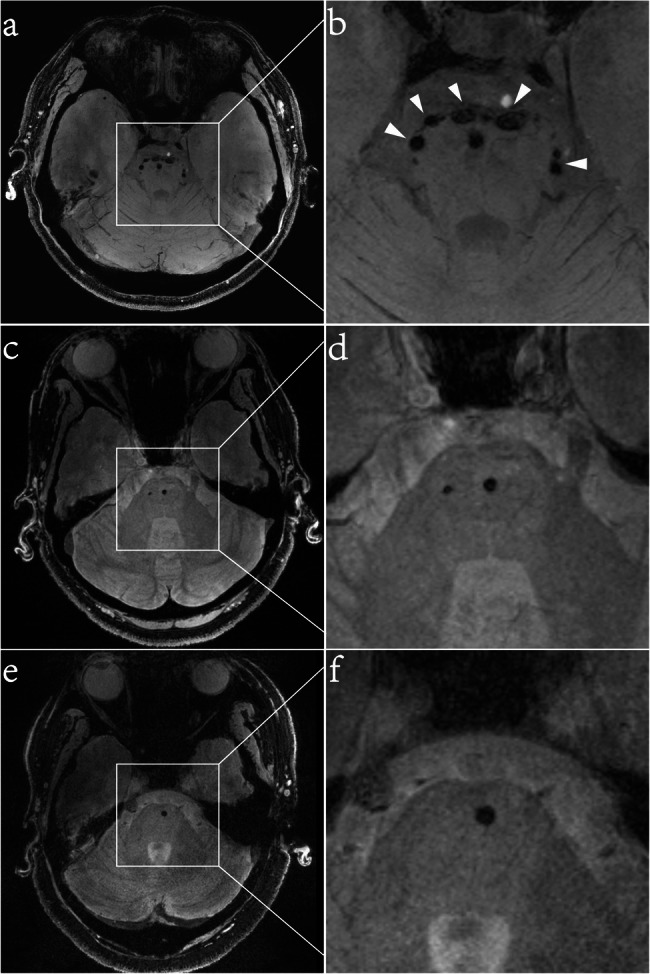

Materials and methods: This cross-sectional study included seven patients with hHTRA1-CSVD, twenty-seven patients with CADASIL and twelve patients with sporadic CSVD. All participants underwent 7.0T magnetic resonance imaging (MRI). The "pons chocolate chip sign" was defined as round or ovoid hypointense dots (≥ 2 mm in diameter) surrounding the pons on T2*-weighted gradient echo images. The number of chocolate chips was independently assessed by two blinded neurologists. Diagnostic performance was evaluated using receiver operating characteristic (ROC) curve analysis, with genetic diagnosis as the gold standard.

Results: The "pons chocolate chip sign" was found in 5/7 patients with hHTRA1-CSVD, compared to 2/27 in CADASIL and 0/12 in sporadic CSVD. ROC analysis revealed that it exhibited good discriminatory capability for hHTRA1-CSVD (area under the curve [AUC] = 0.84, 95% confidence interval [CI]: 0.63-1.00, P = 0.004). At an optimal cutoff of chocolate chips ≥ 1, the sensitivity, specificity, positive predictive value (PPV), negative predictive value (NPV), and Youden index were 71.42%, 94.87%, 71.42%, 94.87%, and 0.66, respectively. When the cutoff was increased to ≥ 3 chocolate chips, the specificity improved further, reaching 100%.